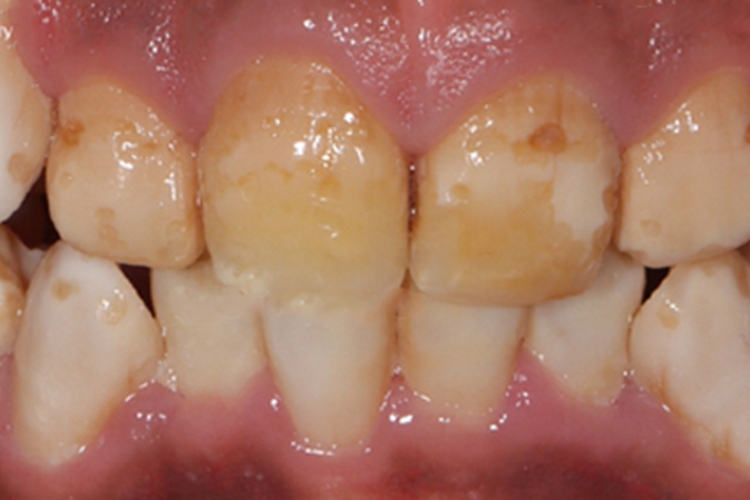

氟斑牙可表现为釉面光泽度改变,牙齿釉面失去光泽,不透明,可见白垩样线条、斑点、斑块。釉面也可出现不同程度的颜色改变,浅黄、深褐色或黑色,着色范围可有细小斑点、条纹、斑块,直至布满大部釉面。

部分患者可出现牙齿釉面缺损,缺损的程度不一,轻者缺损仅限于釉质表层,严重者缺损可发生在所有的牙面,包括邻接面,可破坏牙齿整体外形。